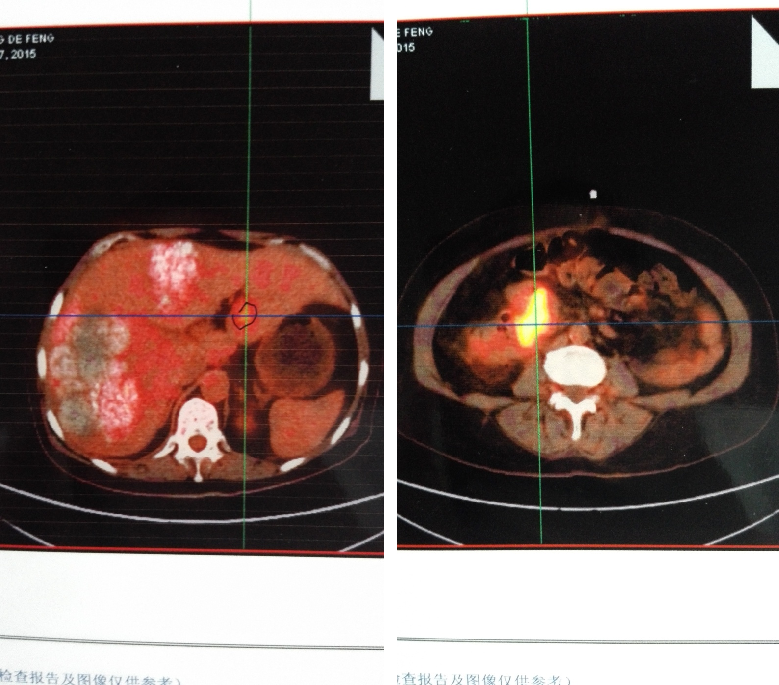

患者左肝为转移病灶,但右肝病灶性质无法明确,进一步行PET-CT检查:

①结肠肝曲肠壁明显增厚,FDG代谢增高,转移可能大;肠周数枚小结节,FDG代谢目前未见明显增高;肝左叶外侧段局灶性FDG代谢增高,MT不除外。

②肝脏明显增大,两叶广泛颗粒样钙化伴局部囊性密度影,考虑肝棘球蚴病可能。